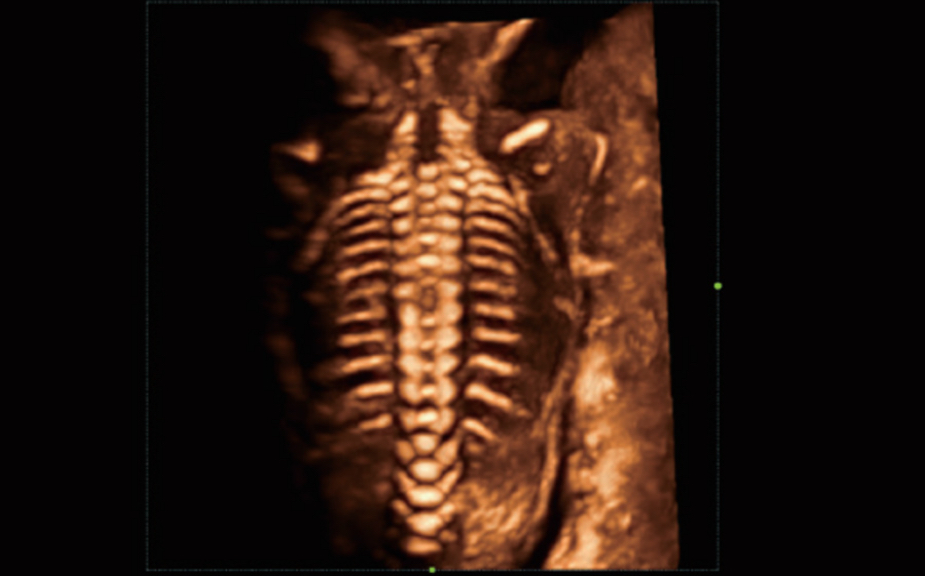

De Nuewa I9, speciaal ontworpen voor vrouwen en neonatale gezondheidszorg, biedt een innovatieve ervaring van binnenuit. Deze innovaties zijn ontwikkeld op basis van diepgaande inzichten in complexe klinische scenario's en bieden nauwkeurige en tijdige antwoorden, evenals een uitstekende effici?ntie en opmerkelijke gebruikerservaring.

Het ZST+ platform is een buitengewone innovatie en revolutie in de wereld van ultrasound. Het transformeert ultrasoundgegevens van conventionele bundelvorming naar kanaalgegevensverwerking. Het overwint de traditionele afweging tussen ruimtelijke resolutie, temporele resolutie en weefseluniformiteit, en levert een uitzonderlijke beeldkwaliteit voor oneindige beeldvormingsoplossingen met non-stop verbeteringen.